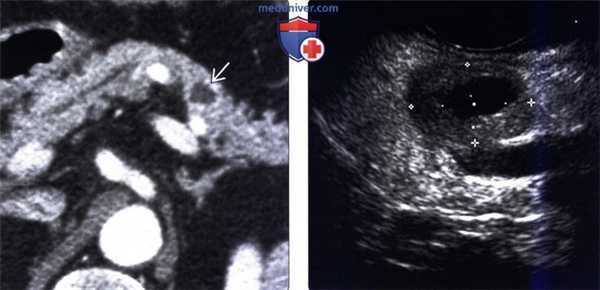

(Слева) На КТ с контрастным усилением, выполненной по поводу пенетрирующей язвы желудка, определяются выбухающие складки вдоль большой кривизны и воспалительные изменения в прилежащей брыжеечной клетчатке. Обратите внимание на отграниченное скопление жидкости, тесно прилежащее к желудку.

(Справа) На рентгенограмме в боковой проекции, выполненной во время рентгеноскопии желудка у этого же пациента, визуализируются утолщенные складки желудка и язва, проецирующаяся за пределами контура желудка по большой кривизне. Расположение язвы соотносится с локализацией жидкости и воспалительных изменений, обнаруженных на КТ.